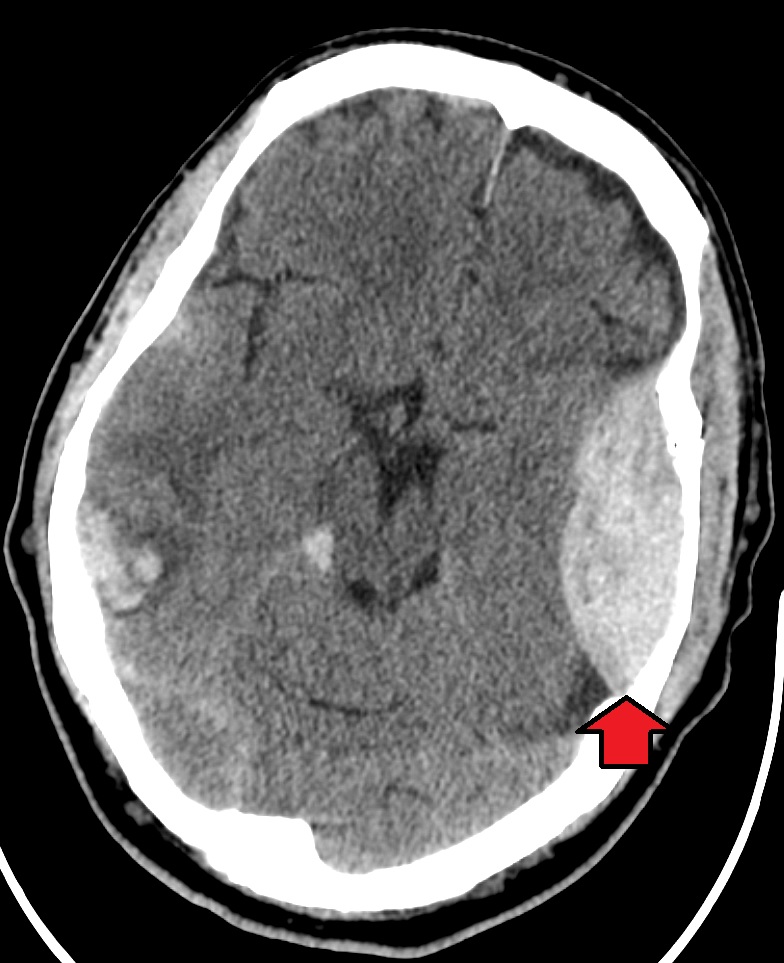

| Subdural haemorrhage | Crescent-shaped hyperdensity along brain surface, crossing suture lines, may track over a large area. Often associated with mass effect and possible midline shift. |

| Epidural haemorrhage | Biconvex (lens-shaped) hyperdensity that typically does not cross suture lines. May cause mass effect and midline shift; commonly related to skull fracture. |

- Midline shift: Displacement of midline structures (falx cerebri, septum pellucidum) suggests mass effect from haemorrhage, tumour or major oedema.

- Haemorrhage: Hyperdense areas. Classify as epidural, subdural, intraparenchymal, or subarachnoid based on location and shape.